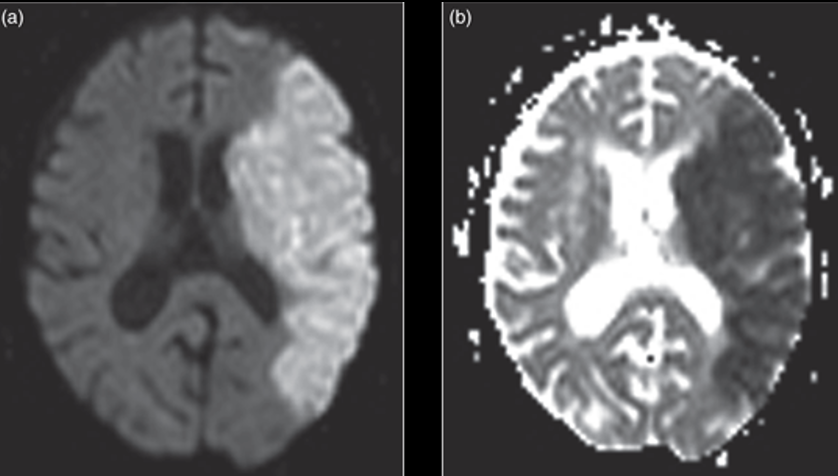

Watershed stroke looks like ______ on imaging

linear pattern